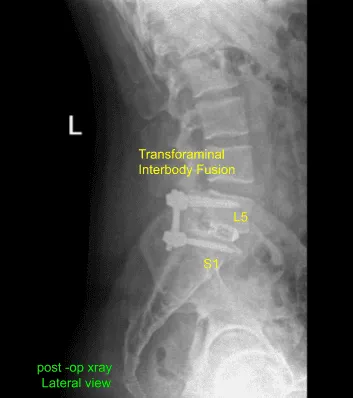

We had discussed treatment options including; surgical and non surgical, both their risks, complications and recoveries. We discussed the use of implants in the form of screws, rods and cage as well as use of biologics such as bone grafts and substitutes from his own bone, cadaveric bone as well as non-human derivatives. We discussed the need for extensive rehab, inability to return to presurgical level among others. Patient agreed with the plan which was a Transforaminal Interbody Fusion (TLIF) L5-S1 electively.

Postoperative X Ray showed there is a normal lumbar lordosis. There were no destructive abnormalities or fractures. The intervertebral disc spaces appear preserved. There was no spondylolisthesis. The facet joints appear unremarkable.

The patient followed up in our office two weeks after the surgery, with their post operative images. During this visit we discussed home exercise programs for rehabilitation of the back. We went over the X Rays and the surgical procedure. They agreed to continue icing to keep the swelling to a minimum and to continue to utilizing early mobilization and mechanical prophylaxis to reduce the chances of a deep vein thrombosis.